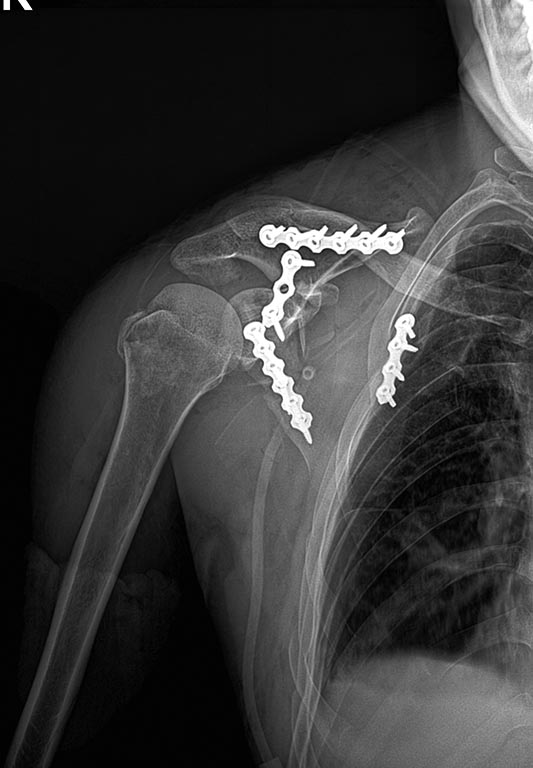

уважаемые коллеги спасибо за участие прооперировали пациента ,вывих плеч

удалось вправить во время синтеза лопатки из доступа Жюде.

потом перевернули и из детьтоидопекторального подшили ротаторы с кусками

бугра. вывих  ключицы не фиксировали.позже сделаем